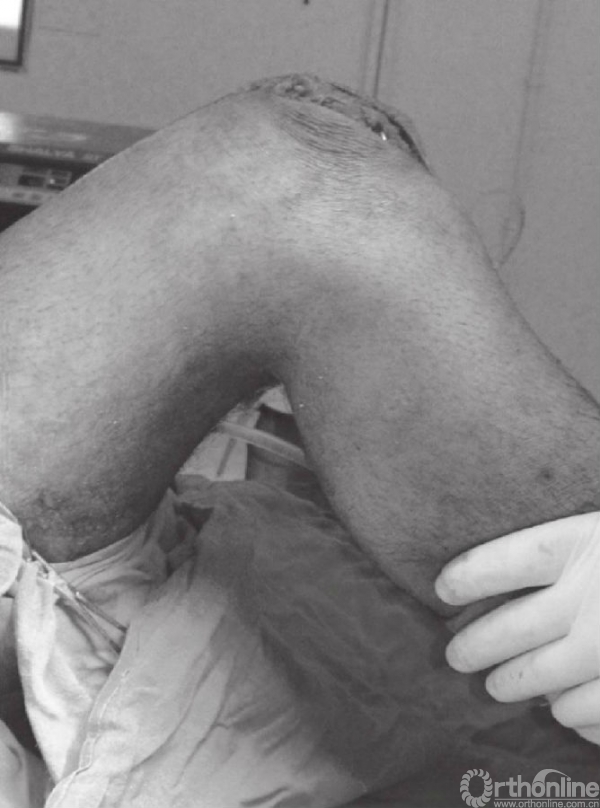

在张力带旋紧固定后,用钢丝剪剪除多余钢丝。突出的部分折弯后贴近髌骨上极放置(图15)。克氏针末端用折弯器折弯后尽量贴近髌骨表面。钢丝末端旋转后经股肌间隙埋入股四头肌腱(图16)。后期缝合肌间隙,可防止克氏针退出。克氏针远端在近髌骨处切断(图17)。用不可吸收线缝合撕裂的支持带(图18)。屈膝90°,以评估内固定的稳定性(图19)。

图19 屈膝90°,评估内固定的稳定性